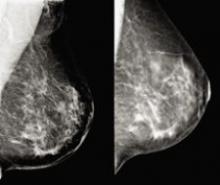

There were notable advances last year in diagnosing and treating breast cancer due in part to the widespread adoption of effective diagnostic tools such as digital mammography, ultrasound, breast MR and PET/CT. Innovation in technology, however, also stirred up controversy in 2007, in particular over the efficacy of computer-aided detection (CAD) as a second read for digital mammography.

The tide may finally be turning in the fight against cancer as the decline in cancer deaths nearly doubled from 2002 to 2004, the American Cancer Society reported in October 2007.1 Early diagnosis enabled by digital mammography and breast MRI are currently building the momentum, but new developments in tomosynthesis, cone-beam CT and biomarkers may be the tipping point.